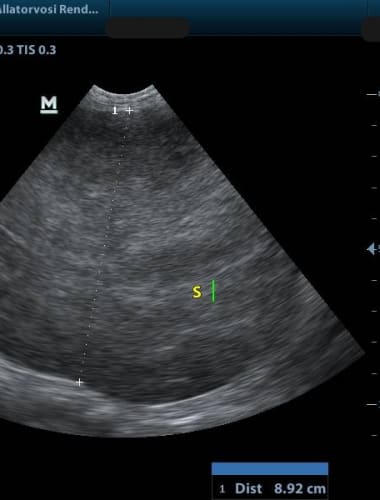

A fokozott nyálzás, véres nyál, rossz szájszag vagy nem gyógyuló bőrelváltozás laphámrákra is utalhat. A diagnózis biopsziával, a kezelés...